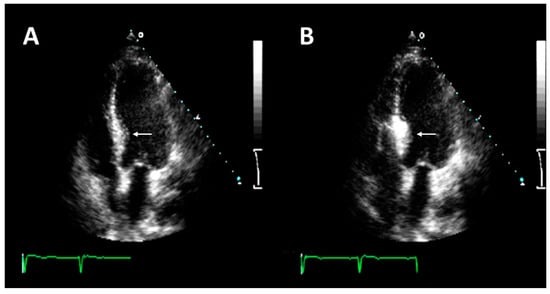

3.2. Pre-Procedural Anatomic Evaluation

3.3. Description of the Procedure